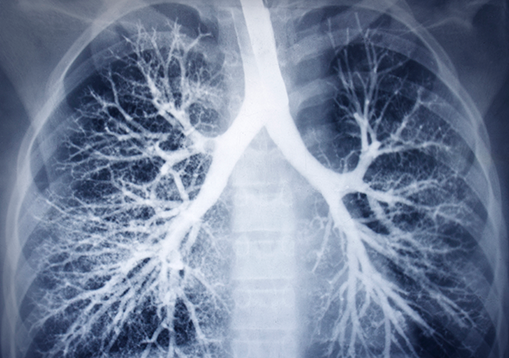

X-Rays of lungs

• Chest x-ray (CXR)